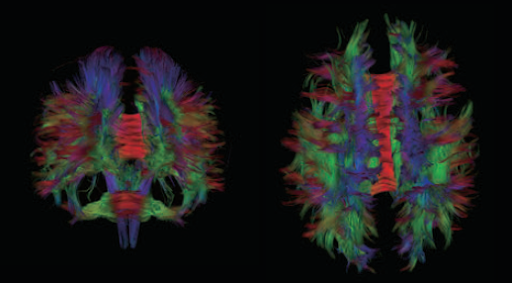

Диффузионно-взвешенное изображение с технологией PUREGradient